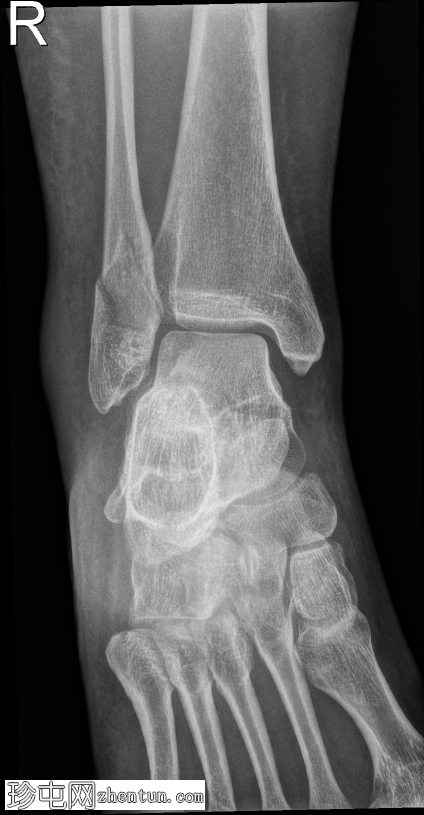

侧位片

腓骨远端在胫腓联合水平处发生螺旋形骨折,符合Weber B型骨折。远端骨折块轻度向外侧移位。距骨在踝关节内也出现向外侧移位。

内侧胫距关节间隙增宽,胫腓骨重叠减少,胫腓间隙增宽。这些发现提示胫腓联合韧带损伤,并提示踝关节不稳。可见轻度软组织肿胀。

病例讨论

这种损伤模式符合Weber B型骨折,是由旋后足受到外旋力所致。骨折发生在胫腓联合处,即连接胫骨和腓骨的韧带群。本例中,踝关节内侧以及胫腓骨之间的间隙增宽,提示这些稳定韧带已受力或撕裂。因此,距骨略微外移,表明踝关节不再处于正常对位,且不稳定。

当踝关节失去这种稳定的对位时,关节无法正常承受重量,若不及时治疗,可能导致疼痛、持续不稳定以及关节早期磨损。由于这种不稳定性,此类骨折通常采用手术固定治疗,以重新对位并固定踝穴,从而确保骨折愈合,并降低长期并发症的风险。

患者已用膝下硬石膏固定,并转诊至骨科团队进行切开复位内固定术。